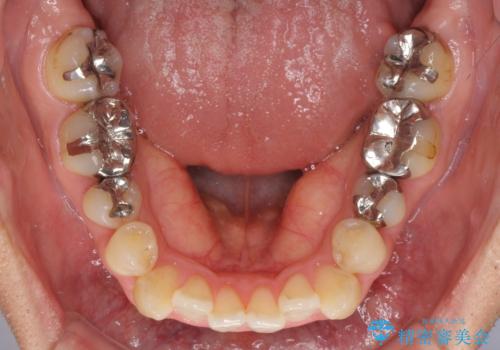

奥歯には目立つ銀歯が多くあるので、矯正治療後には下顎の銀歯をセラミッククラウンやセラミックインレーにより、補綴・修復治療することとしました。

上顎歯列全体を後方に移動させたため、口元の突出感も改善され、装置を外してからは口が閉じやすくなりました。

また、上下犬歯が接触するようになったため、奥歯にストレスのかからない歯ぎしりができるようになり、顎の疲れも改善されました。